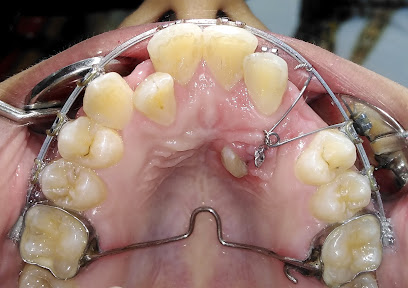

سمايلي كلينيك لطب وتقويم الأسنان في أسيوط هو المكان المثالي لعناية بصحة وجمال أسنانك. يقدم العيادة خدمات طبية متخصصة تشمل تقويم الأسنان وعلاجات دواعم الأسنان بجودة عالية ورعاية فائقة. للحجز والاستفسار، يُرجى الاتصال على رقم الهاتف التالي: [رقم الهاتف].